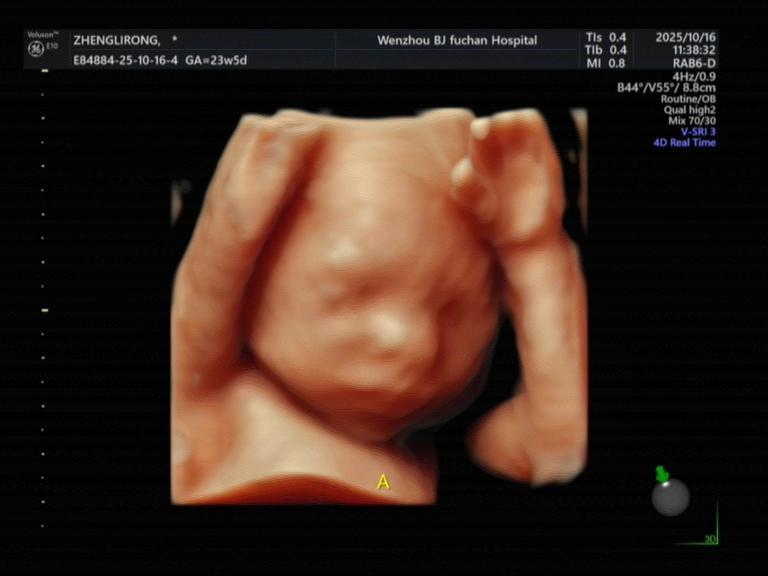

医院用的美国GE Voluson E10设备,宝宝五官看得超清晰